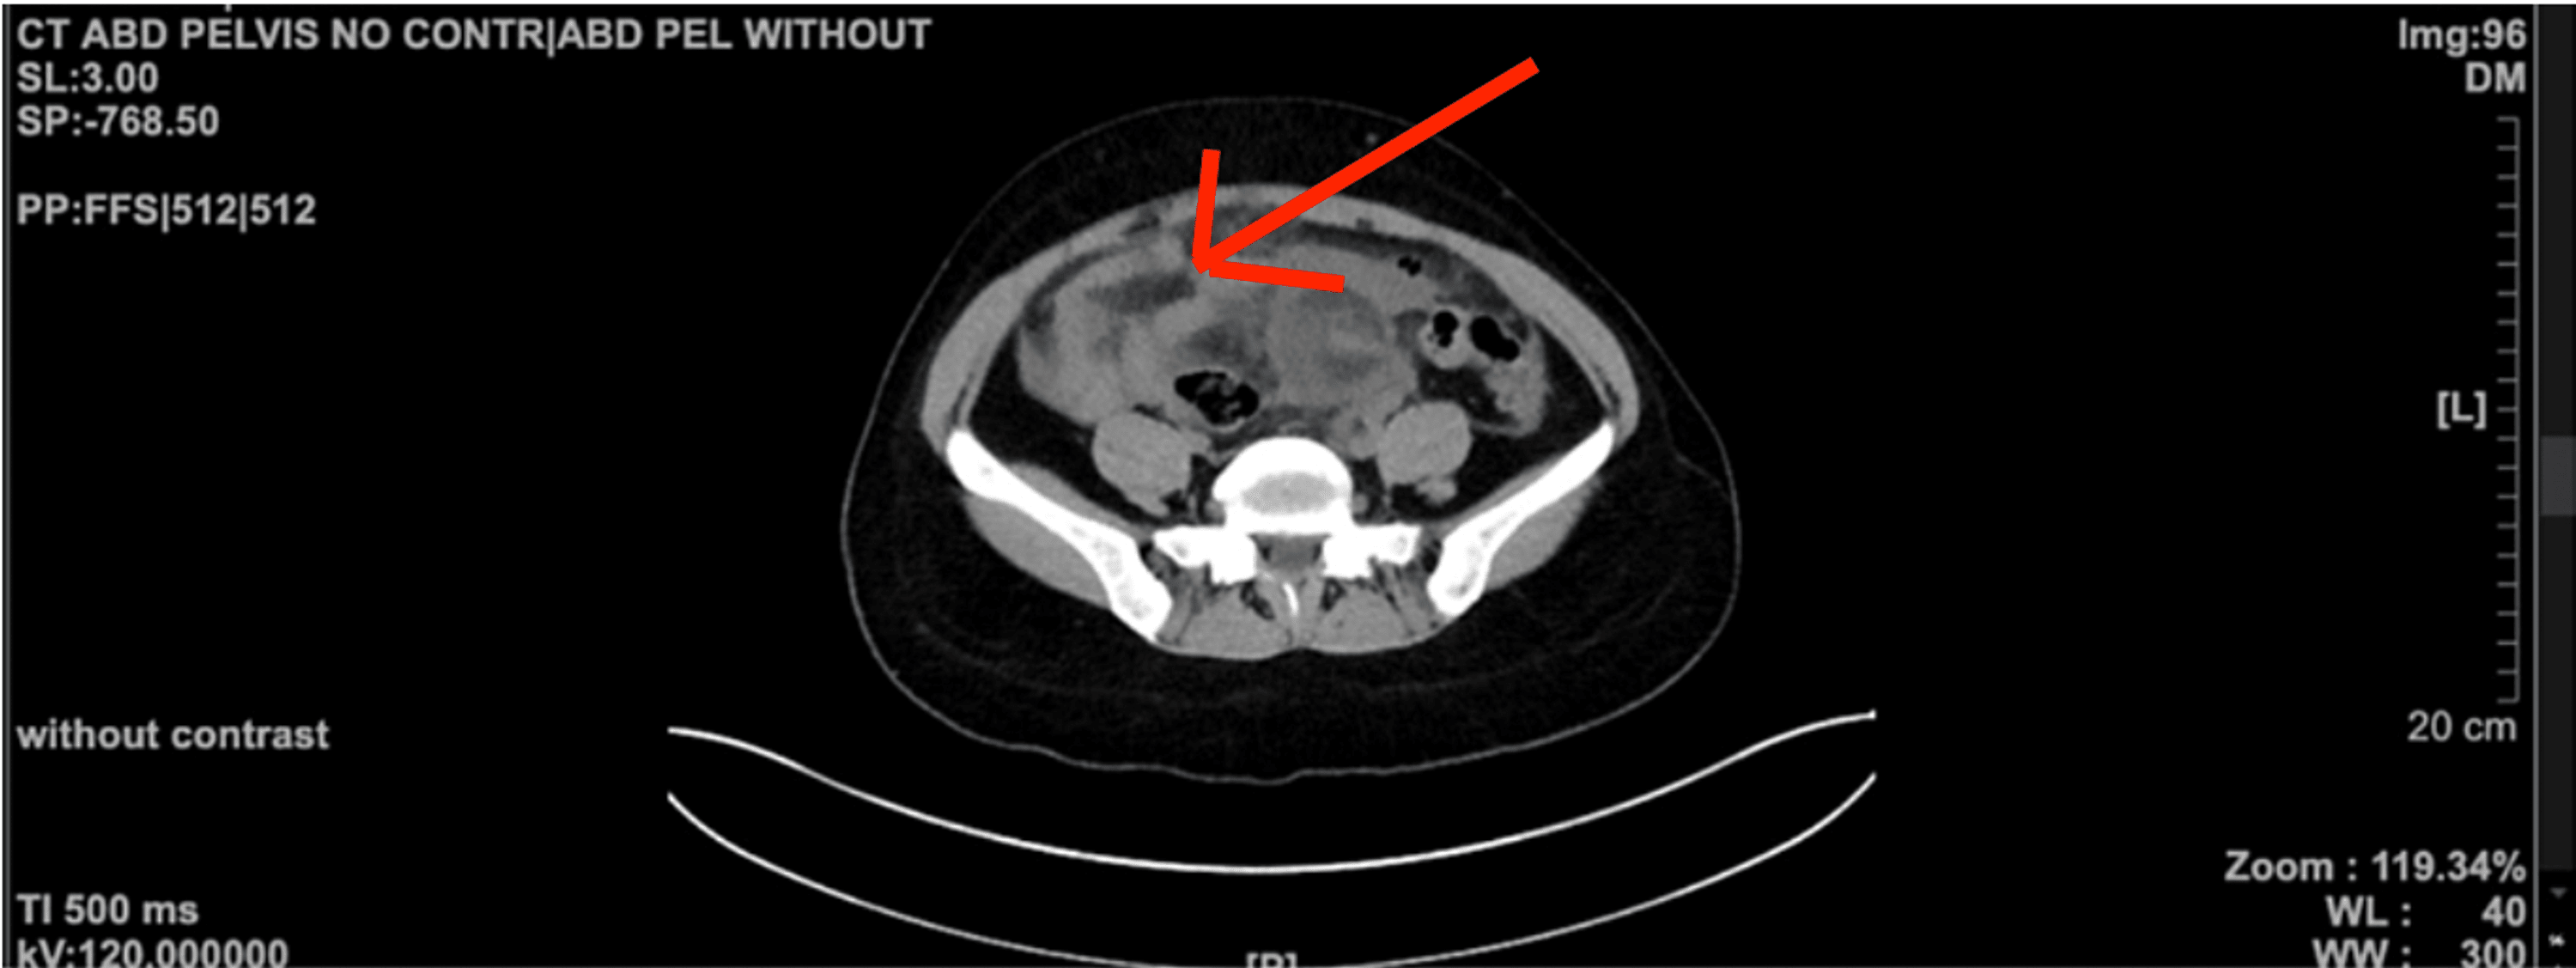

Percutaneous Abscess Drainage Quickloop Abscess Treatment Device learn how to use the quickloop device and how it can benefit. find detailed product information including brand name, issuing agency, model number, company name and more of product. compared with standard incision and drainage, the loop drainage technique was equally effective in adults,. em device lab of austin, tx provides an innovative solution for the. Quickloop Abscess Treatment Device.